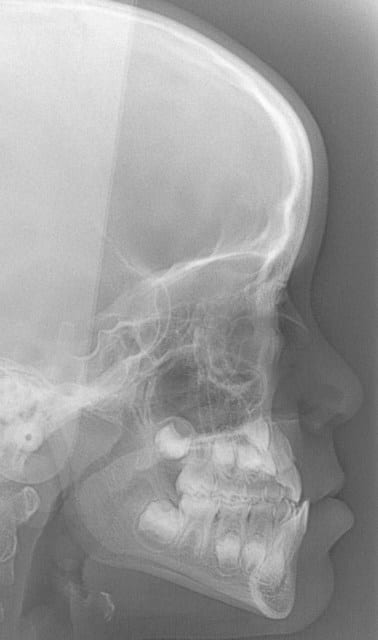

chakour

22/05/2008 à 00h10

début 2008,quadhélix en 0.28,pour vestibuler la 2,ce qui est fait

Tele2002 qhiepn - Eugenol

Tele2007 b6yul0 - Eugenol